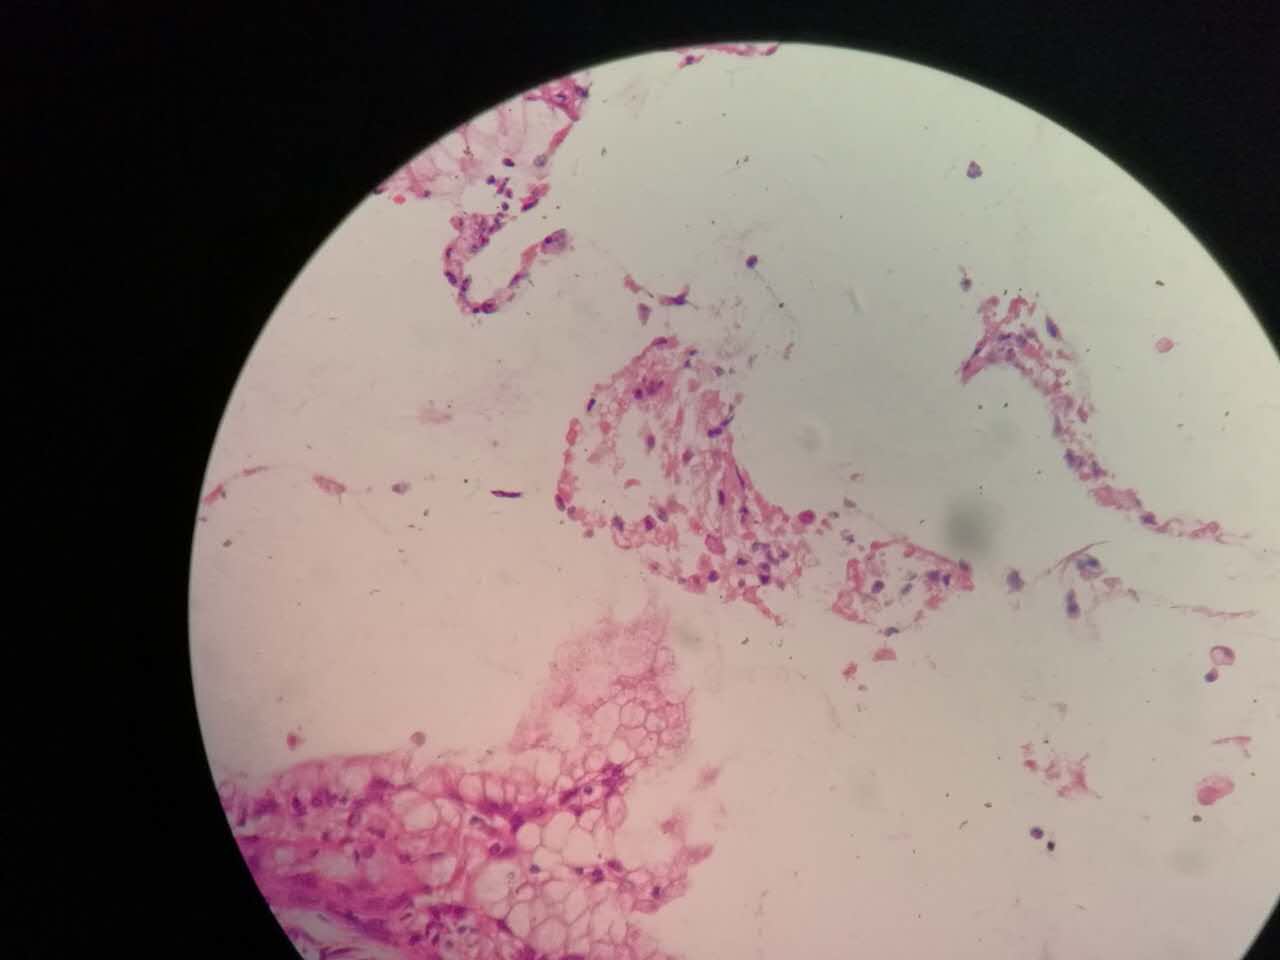

粘液型腺癌的肿瘤细胞排列整齐,核位于基底,细胞呈柱状。

肺泡间隔(间质)经常比较细

差不多都长这样

这个生长密集,相对要重

这个细支气管,一半癌浸润

肿瘤细胞形态仍然相似

中央有个肺血管,说明破坏力不强

也会有些坏死,连同粘液咳出去,就形成实变区内的空洞